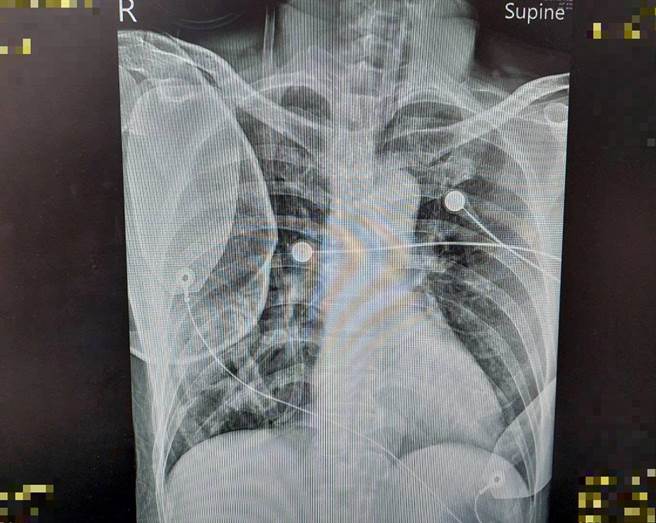

病患失去呼吸心跳后,经CPR及电击才顺利恢復自发性心律,但呈现深度昏迷状态。(大千医院提供/谢明俊苗栗传真)

体内式低温疗法是以植入式导管中的液体,来协助降低体温。(大千医院提供/谢明俊苗栗传真)